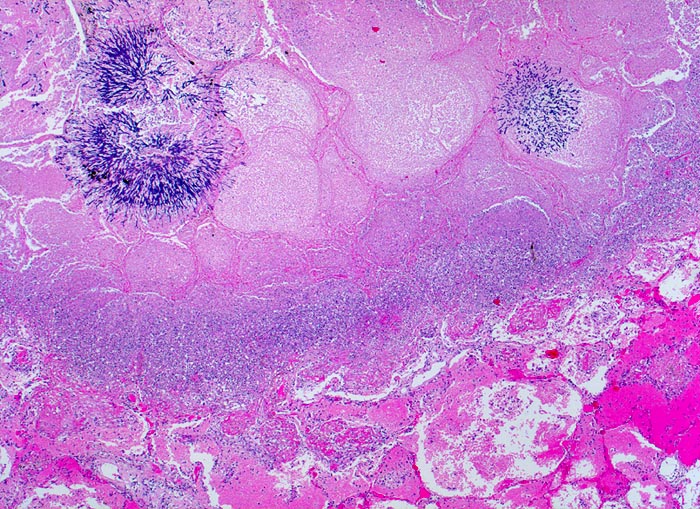

PathoPic – image database / PathoPic ID 4823 - Aspergilluspneumonie

Aspergilluspneumonie

Zwei Pilzkolonien im Zentrum der Gewebsnekrose. Angrenzend an das Nekroseareal folgt ein Saum von zerfallenden neutrophilen Granulozyten (blau) und weiter aussen der hyperämische Randsaum mit den Fibrinexsudaten.

Seit 14 Monaten bekannte chronische lymphatische Leukämie behandelt mit Chemotherapie. Der Patient entwickelt unter Therapie eine Pneumonie und verstirbt an einer Pilzsepsis.